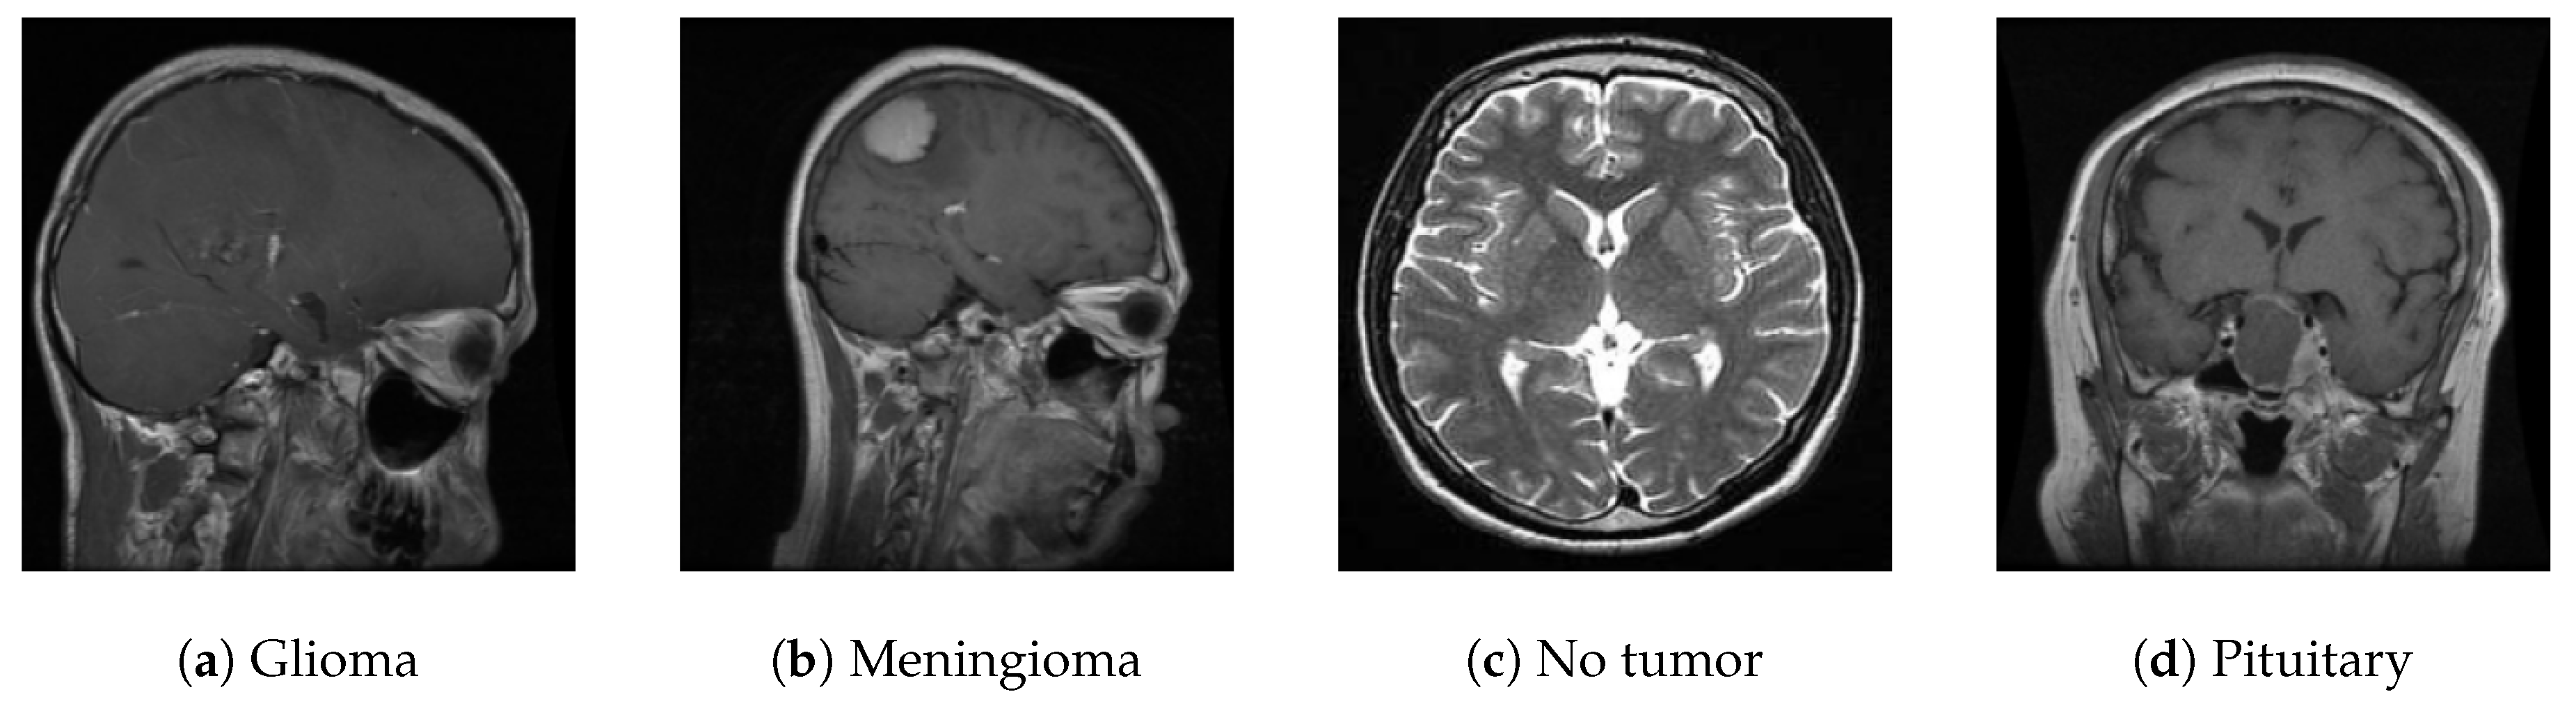

For this study, we utilized a publicly available MRI dataset from Kaggle [36], comprising 7,023 brain MRI images sorted into four categories: glioma, meningioma, pituitary, and no tumor. This dataset integrates images from several sources, including figshare [37], the SARTAJ dataset [38], and Br35H [39], with non-tumor images primarily sourced from Br35H. Figure 10 illustrates the distribution of these images across each category, while Figure 11 presents sample images from each class.

Figure 11. Samples from the dataset.